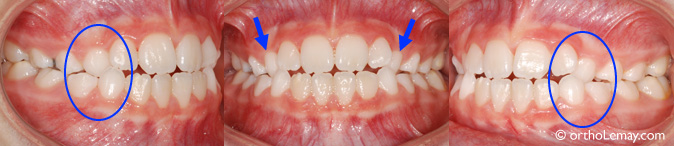

(A) Avant l’expansion, les incisives centrales supérieures sont droites.

(B) À la fin de l’expansion, un espace important apparaît entre les incisives centrales qui sont toujours droites (flèches). (À noter le problème d’hygiène et l’accumulation de plaque dentaire.)

(C) Après quelques mois, les incisives centrales ont récidivé vers le centre, mais se sont aussi inclinées vers le centre, ce qui peut se produire à l’occasion. Ceci sera corrigé lors d’une étape ultérieure.

Bien qu’une telle variation dans la position des dents puisse occasionner un léger préjudice esthétique dans certains rares cas, cela ne cause habituellement pas de problème fonctionnel. Il faut aussi se rappeler que l’expansion n’étant qu’une première phase de traitement, d’autres corrections seront de toute façon nécessaires plus tard pour finaliser et optimiser la position des incisives et toutes les irrégularités pourront alors être corrigées. De plus, il est possible que ces dents se déplacent à nouveau lorsque les canines permanentes feront éruption.